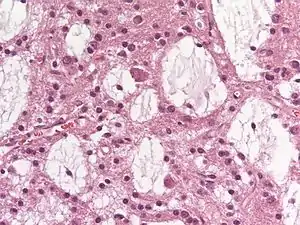

Dysembryoplastic neuroepithelial tumours are largely glioneuronal tumours, meaning they are composed of both glial cells and neurons.[2]

Three subunits of DNTs have been commonly identified:[2]

• Simple: Specific glioneuronal elements are the sole components of simple DNTs.[2]

• Complex: Glial nodules and/or type 3b focal cortical dysplasia (FCD), in addition to the glioneuronal elements are present in complex DNTs.[4] Both the nodules and FCD can be present within the same tumour, though only 47% of complex DNTs are linked to FCD.[2]

• Nonspecific: Nonspecific DNTs are lacking the glioneuronal elements common to DNTs but will show glial nodules and/or type 3b FCD.[2] Eighty-five percent of nonspecific case of DNTs show this FCD.[2]